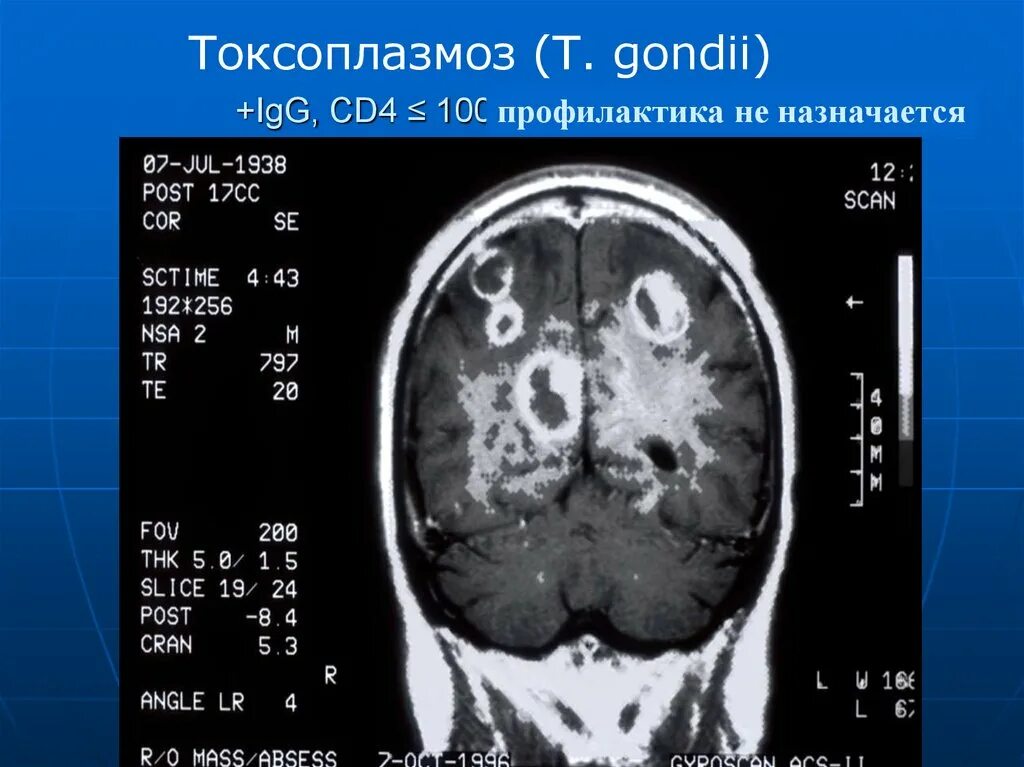

Токсоплазмоз у вич инфицированных